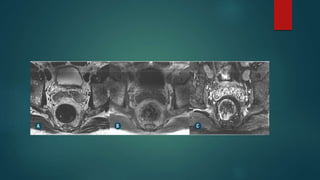

VESICULITE SEMINAL AGUDA

 Geralmente secundária a prostatite bacteriana e apresenta-se na

US, TC ou RM com espessamento parietal ,além de impregnação

parietal difusa pelo contraste na TC e RM.